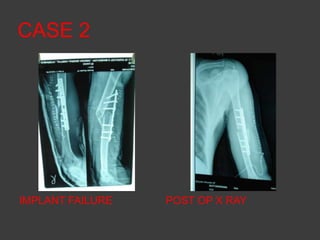

CASE 2

IMPLANT FAILURE   POST OP X RAY